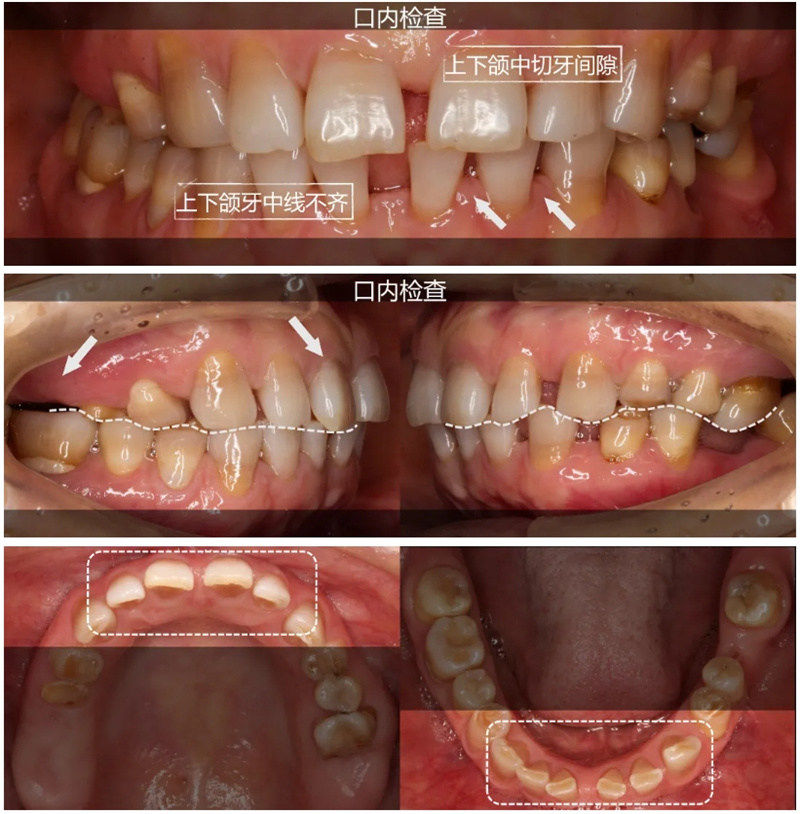

鑿山開(kāi)路辟通途——前牙復(fù)雜病例聯(lián)合修復(fù)

陜西定遠(yuǎn)齒科技術(shù)有限公司與空軍大學(xué)口腔修復(fù)科共同完成復(fù)雜前牙散在間隙伴牙列缺損患者的正畸-種植-修復(fù)聯(lián)合*。